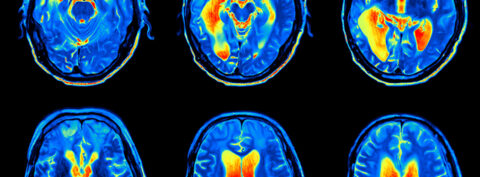

La polisomnografía es una técnica que permite estudiar el sueño y sus fases mediante el registro de diferentes variables fisiológicas como la presión arterial, la actividad electroencefalográfica, ocular, muscular, cardiaca y respiratoria.